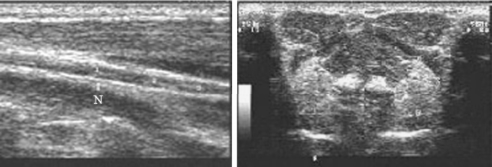

神经:频率8~12MHz探头,较粗的神经为低回声,神经束及表面的鞘为高回声,纵切呈束条样,内血流不能显示(图6-2左)。

图6-2 迷走神经及舌下腺二维超声图

左图为迷走神经纵切面;右图为正常双侧舌下腺

涎腺:颌面部3对较大的涎腺声像图均能显示。内部为中等密集回声。腮腺及颌下腺浅筋膜边界清楚,腮腺深面边界不清楚。颌下腺深部与舌下腺相邻的部分两者图形类似不易分清边界。舌下腺周边包膜回声不明显。外形:腮腺纵切呈梭形,横切呈楔形;颌下腺纵切为长三角形,横切近等边三角形;舌下腺横切为类圆形(图6-2),纵切前后径稍大于横径。用分辨力甚高的机型可显示腮腺及颌下腺的主导管,纵切呈细管道样,直径0.3~1mm,口含酸性食物后涎液分泌增多,导管增粗,液区易显示(图6-2右)。三对大涎腺超声测值见表6-1。